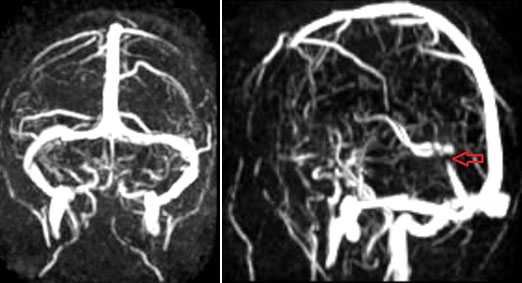

МРТ головного мозга: справа (зеленая стрелка) на Т2-взвешенном изображении отмечается имеющийся в норме феномен «пустоты потока» от правого сигмовидного синуса и яремной Вены. Слева (оранжевая стрелка) отмечается аномально высокий сигнал, в результате, вероятнее, тромбоза. Для подтверждения синус-тромбоза и окончательного определения локализации и протяженности тромбоза необходимо проведение МР-венографии.

МР-венография: тромбоз левого поперечного синуса. Отмечается потеря МР-сигнала от левого поперечного синуса.

Наличие визуализации синуса на «сырых» данных или же МРТ головного мозга подтверждает тромбоз синуса и исключает его гипоплазию.

МРА-картина выраженной асимметрии венозной сети с преобладанием и нерезкой дилатацией вен правой гемисферы (поперечного, сигмовидного синусов и яремной вены справа); гипоплазии левого поперечного и сигмовидного синуса. Единичные участки (2) локального расширения вен в парасагиттальных отделах левой гемисферы, большой вены мозга. Асимметричная, расширенная и выражено извитая венозная структура экстракраниальных отделов справа.

МРА признаки незначительной дилатации верхнего сагиттального синуса, локального снижения кровотока и сужения просвета дистальных отделов прямого синуса; асимметрии просвета поперечных, сигмовидных синусов и внутренних яремных вен.